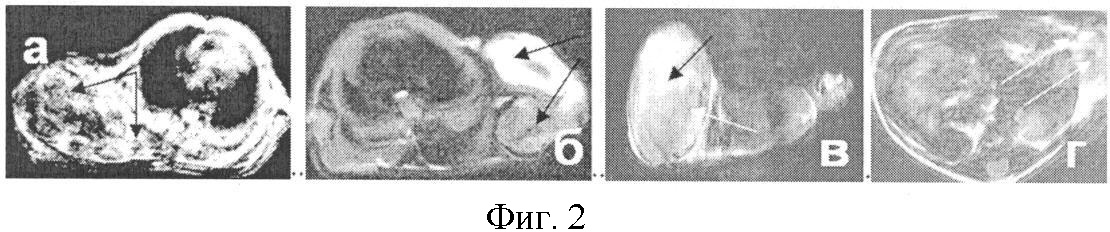

За 36 часов до опыта в хвостовую вену мышей 5-й группы вводят 40 мкл 1% золя декстранферрита в полиглюкине (наночастицы диаметром 20-60 нм; до 2,92 мг Fe/кг) за 10 минут до проведения магнитно-резонансной томографии в хвостовую вену мышей вводят 5 мкл дотарема и 5 мкл магневиста с последующим проведением Т2– взвешенной последовательности. Измеряют повышение интенсивности (яркости) сигнала и повышение контраста изображения, проводят визуальный анализ структуры опухолей и внутренних органов на содержание метастазов. Сравнивают изображения на томограммах, контрастированных декстранферритом, магневистом или дотаремом по отдельности и в комбинациях (фиг.2).

При усилении контраста изображений на томограммах биологических тканей наночастицами декстранферрита в комбинации с дотаремом и магневистом обнаруживаются метастазы в легких, почке и мочевом пузыре (фиг.2, стрелки).